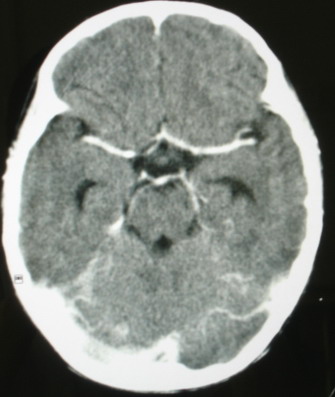

ct意见:1、颅内血管畸形。2、右侧海绵窦血管瘤(颈内动脉海绵窦段动脉瘤)。3、脑萎缩。4、建议mr或dsa.

增强片